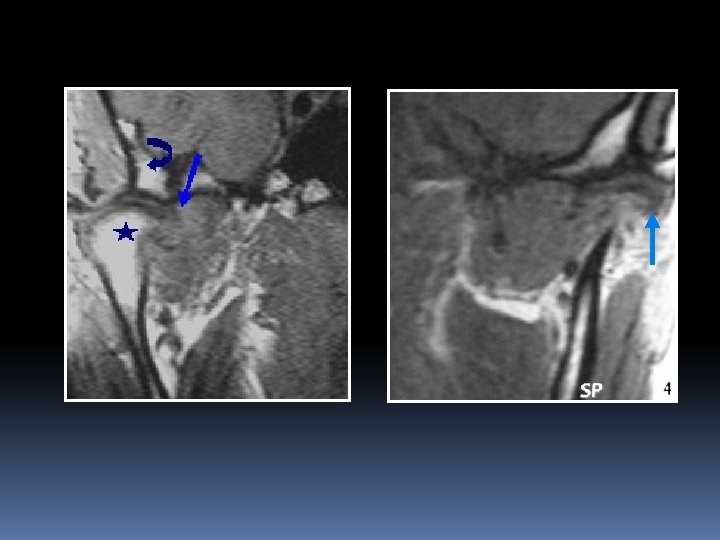

Cavité articulaire Corrélation : importance du volume de l’épanchement / gravité des lésions / douleur Marqueur d’une atteinte dégénérative Importance de sa détection → en l’absence d’une thérapeutique adéquate : Adhérences discales Dégénérescence discale progressive OCD ou ONA Arthrose → déséquilibre occlusif + perte de la valeur fonctionnelle

Signes de dégénérescence articulaire Remodelage articulaire Pincement interligne articulaire

Sclérose chondrale Ostéophytose

Œdème spongieux T 2 T 1 D D G Ostéochondrite G T 1 Gado disséquante D Otéonécrose aseptique G